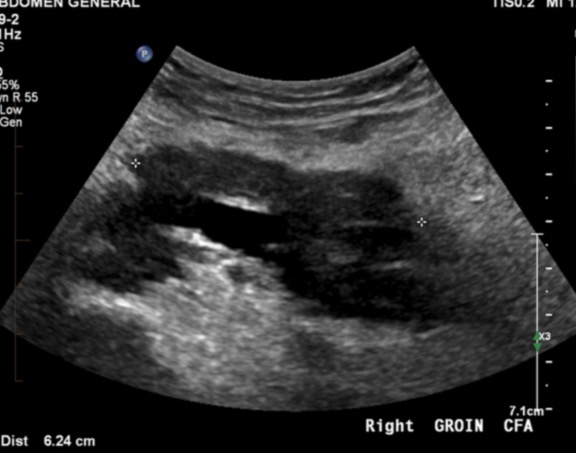

70 male prostate CA with groin mass

FEMORAL ARTERY LEIOMYOSARCOMA WITH BONE METASTASES.

Vascular leiomyosarcoma ( RID4387 )